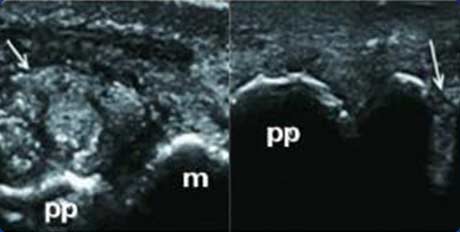

����������ʾ���DZ��������νᾧ����״�� �ж�ʹ����������

���dz�����ͨ������Ӱ��ͼ�ж����DZ���������һ����ǿ������Ƥ��ƽ�е�����ǿ��������“˫����”��һʹ���Թؽ��������Ա��֣��ж�������������������ճ����������Ư���Ļ�Ĥ��ʱ�����������ڹؽ�ǻ�ڷ���Ư���ĸ�������;���������γ��ڳ������ʹ���ʱ���ڳ����м���ʾ����״���Ը���(�ʹ�)�г��ָ����㡢������������ſ�(������)���Ӷ��ж�ʹ�粡�鴦����һʱ�ڡ�

“˫����”

��ֺ�ؽ����DZ���ɼ�������������ǿ�����ǻ�Ĥ��Ե�ߣ���“˫����”��

������

���DZ��������ǿ��������Ĺ��Թؽ���ǿ�������γ�“˫����”��

�ۼ���

�����ǵ�˫����״����ʾ�����ڲ��ľۼ���